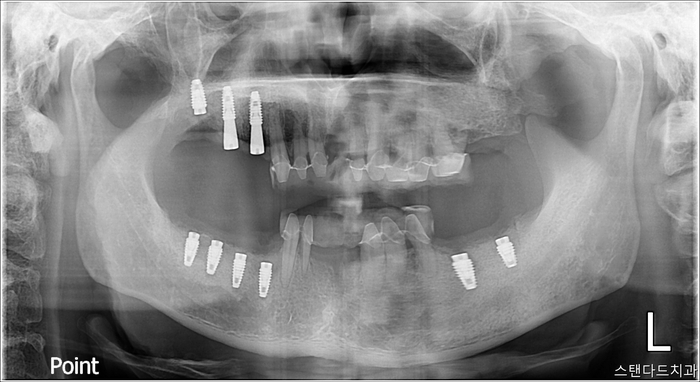

촬영:2023년7월22일

어금니 쪽을 눈여겨보시면

치아가 잇몸에 붙어있는지, 떨어져 나왔는지

구분이 안될 정도로 어금니가 망가져 있는 것이 보이는데요

충치로 인한 염증 때문에

잇몸흡수가 계곡의 형태인 V자로

깊숙하게 패어 있습니다.

다행히 보이는 상태에 비해 남아있는 턱뼈가 좋아

염증을 제거하고 잇몸뼈이식을 추가적으로 해준다면

충분히 회복될 수 있어 보이는 상태입니다.

(연령대가 비교적 젊어서 그런지 잇몸뼈가 단단한 편이세요)

식립한 임플란트는 결과적으로

ISQ 측정 시 60 이상의

안정적인 고정력 수치를 보여주었습니다.